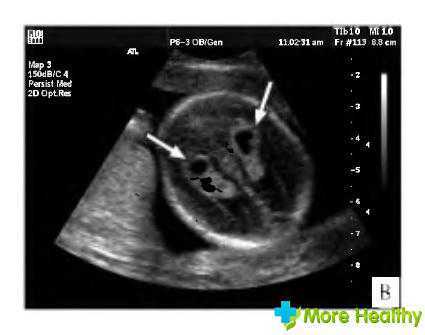

Сосудистые сплетения у плода образуются на сроке 18-19 недель. Именно в этот период, при проведении УЗИ могут быть обнаружены первые признаки кист, которые выглядят, как эхонегативные образования. Чаще всего в срок от 20 до 24 недель, когда идет активное формирование головного мозга, размер кисты уменьшается, и она полностью исчезает.

Образование подобного полостного сплетения, расположенного в правом желудочке мозга, является односторонним. Если у ребенка есть генетические отклонения в структуре мозга, там возможны аномальные изменения. Их легко увидеть во время ультразвукового исследования.При расположении кисты в боковом сплетении наблюдается пониженное ХГЧ, что указывает на врожденную аномальную патологию.

Встречаются также билатеральные кистозные образования сплетений сосудов в мозговых тканях, которые являются двусторонними поражениями. Структура тканей и сосудов мозга не нарушается, но при этом киста затрагивает сплетения сосудов одного бокового желудочка или обоих.